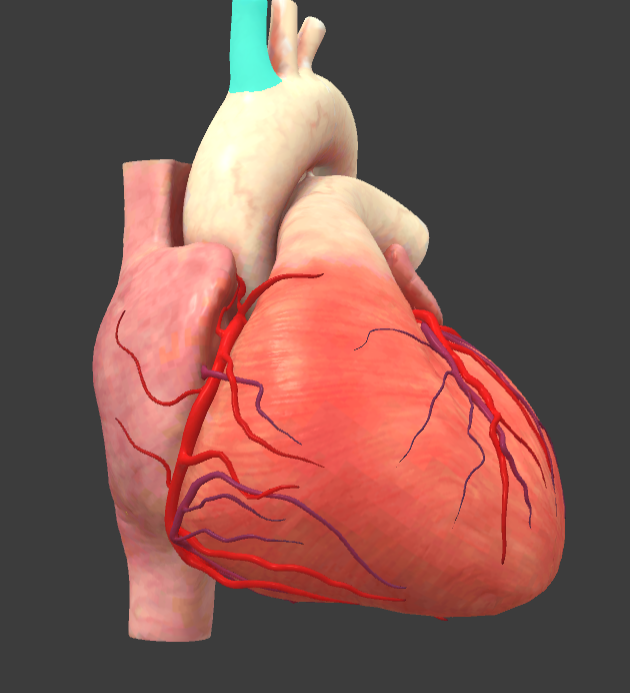

What is the name of the main vessels that supply the heart tissue with blood?

Coronary arteries

Right coronary a.